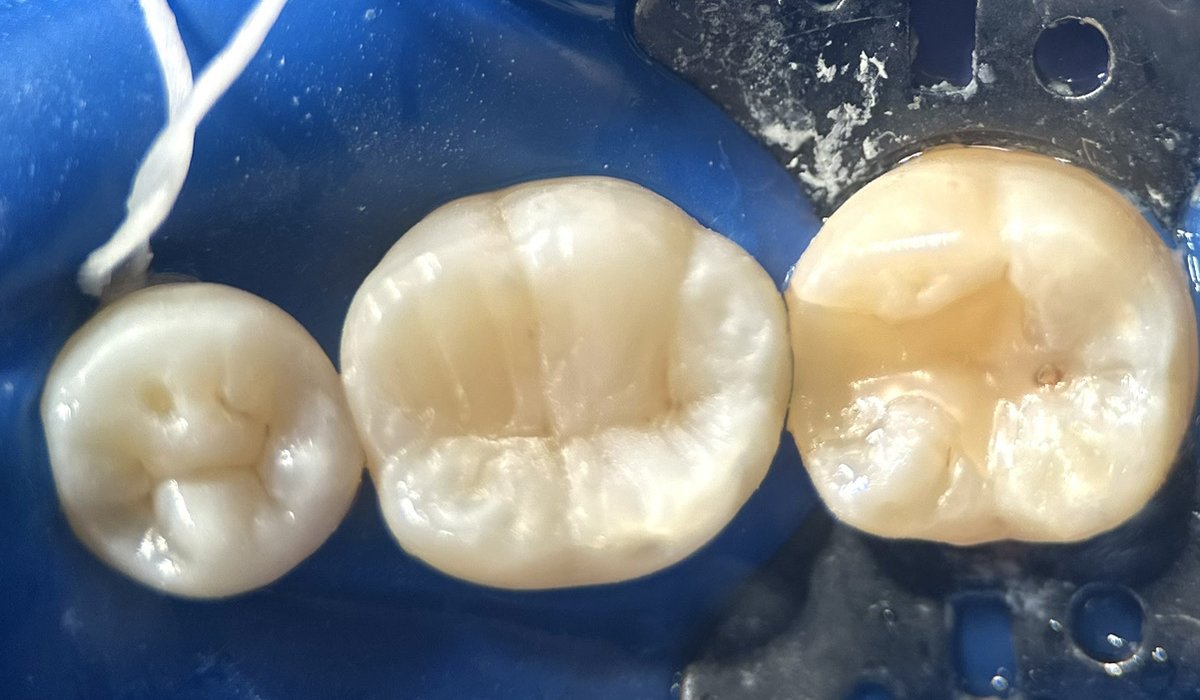

- 虫歯の詰め物

虫歯の治療後今まで銀歯を被せていたケースも、ダイレクトボンディングを用いて自然な歯になりました。